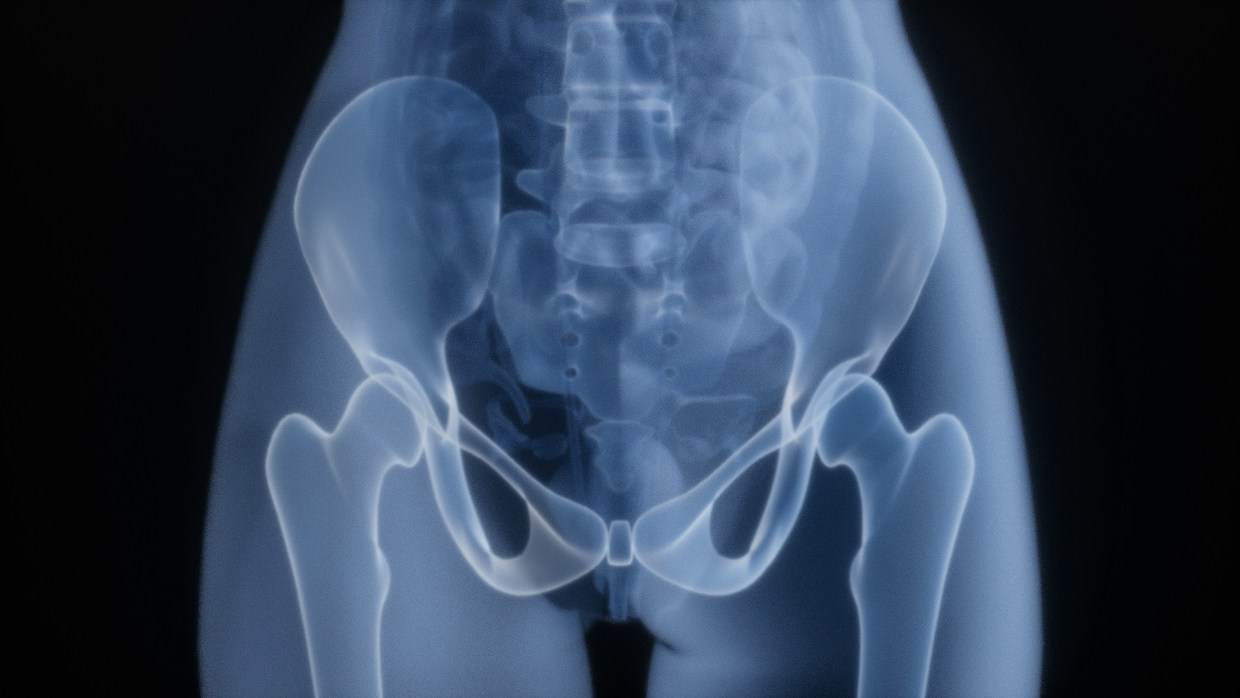

A study involving over 9,700 U.S. women aged 65 and older found that tea drinkers had higher hip bone mineral density compared to non-tea drinkers. Coffee consumption showed neutral effects on bone density, except for those drinking five or more cups daily, who had lower total hip BMD. The study noted interactions with BMI and alcohol intake, indicating that tea was beneficial for women with obesity, while coffee's effects varied based on alcohol consumption. Limitations included self-reported data and a predominantly White cohort.